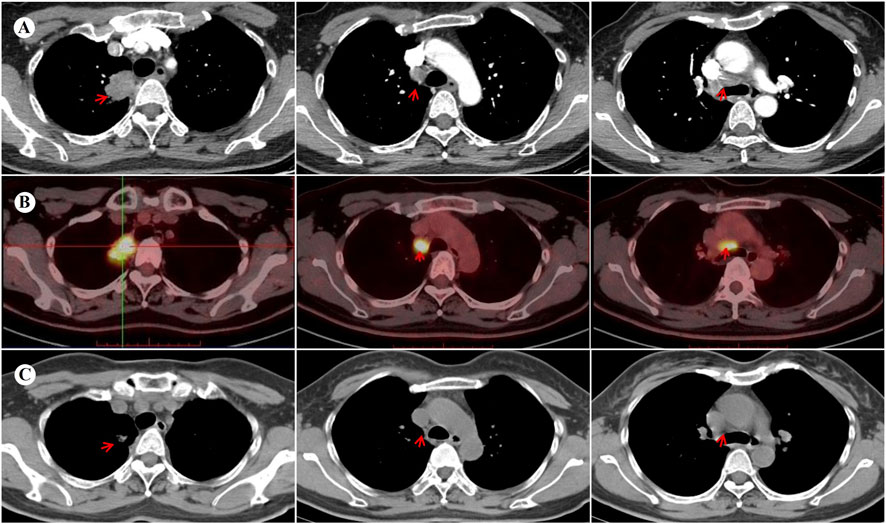

A 45-year-old Chinese woman incidentally presented with a 32 × 24 mm mass in the right-upper lung lobe with enlarged mediastinal nodes (stations 2R and 4R per IASLC classification) on chest computed tomography (CT) images during a checkup visit on 14 November 2023. The findings were suggestive of lung cancer with possible lymph node metastases (Figure 1A). The patient was asymptomatic at presentation, with unremarkable physical examination and an Eastern Cooperative Oncology Group (ECOG) performance status of 0. The medical history was notable for being negative regarding active/passive smoking, excessive alcohol consumption, and occupational carcinogen exposure. Family history was unremarkable for hereditary cancer syndromes or genetic disorders, with no documented malignancies in first-degree relatives across three generations. Bronchoscopy was unremarkable; however, CT-guided transthoracic needle biopsy of the pulmonary lesion confirmed invasive adenocarcinoma. Staging magnetic resonance imaging (MRI) of the brain and positron emission tomography (PET)-CT (Figure 1B) confirmed cT2N2M0 (AJCC, 8th edition) disease. Next-generation sequencing (NGS) identified an EML4-ALK fusion (E6:A20) and TP53 mutation with programmed death-ligand 1 expression corresponding to a tumor proportion score of 1%.

Figure 1. Images before and after neoadjuvant targeted therapy with ensartinib. (A) Contrast-enhanced chest CT at baseline demonstrates a 32 × 24 mm mass with heterogeneous enhancement in the right upper lobe, accompanied by enlarged mediastinal lymph nodes (stations 2R/4R). (B) The baseline PET-CT performed on 21 November 2023 reveals hypermetabolism in the primary lesion (maximum standardized uptake volume [SUVmax] 14.8) and mediastinal lymph nodes (SUVmax 15.5), without distant metastasis. (C) Follow-up lung CT at 3 months post-neoadjuvant therapy shows a significant reduction of the primary lesion (11 × 7 mm) and mediastinal lymph nodes, indicating a partial response (PR) to ensartinib. CT, computed tomography; PET, positron emission tomography.

Given the metastatic involvement of upper mediastinal lymph nodes (station 2R), the surgical outcome was initially classified as an uncertain resection [R(un)]. Following multidisciplinary consensus, neoadjuvant ensartinib 225 mg daily was initiated on 11 December 2023. No significant adverse effects were observed. Imaging after 3 months revealed a partial response (PR) per RECIST 1.1 criteria, with significant regression of the primary lesion and metastatic lymph nodes (Figure 1C). Subsequently, the patient underwent a right-upper lung lobectomy with systematic lymph node dissection on 15 March 2024. Postoperative pathology confirmed an MPR in the primary lesion, with <10% viable tumor cells and accompanied by abundant foam cells and lymphocytes. Notably, the resected lymph nodes demonstrated complete pathological clearance of malignant cells. Final pathological staging was designated as pT1bN0M0 according to the AJCC eighth edition criteria. Adjuvant ensartinib maintenance was recommended.